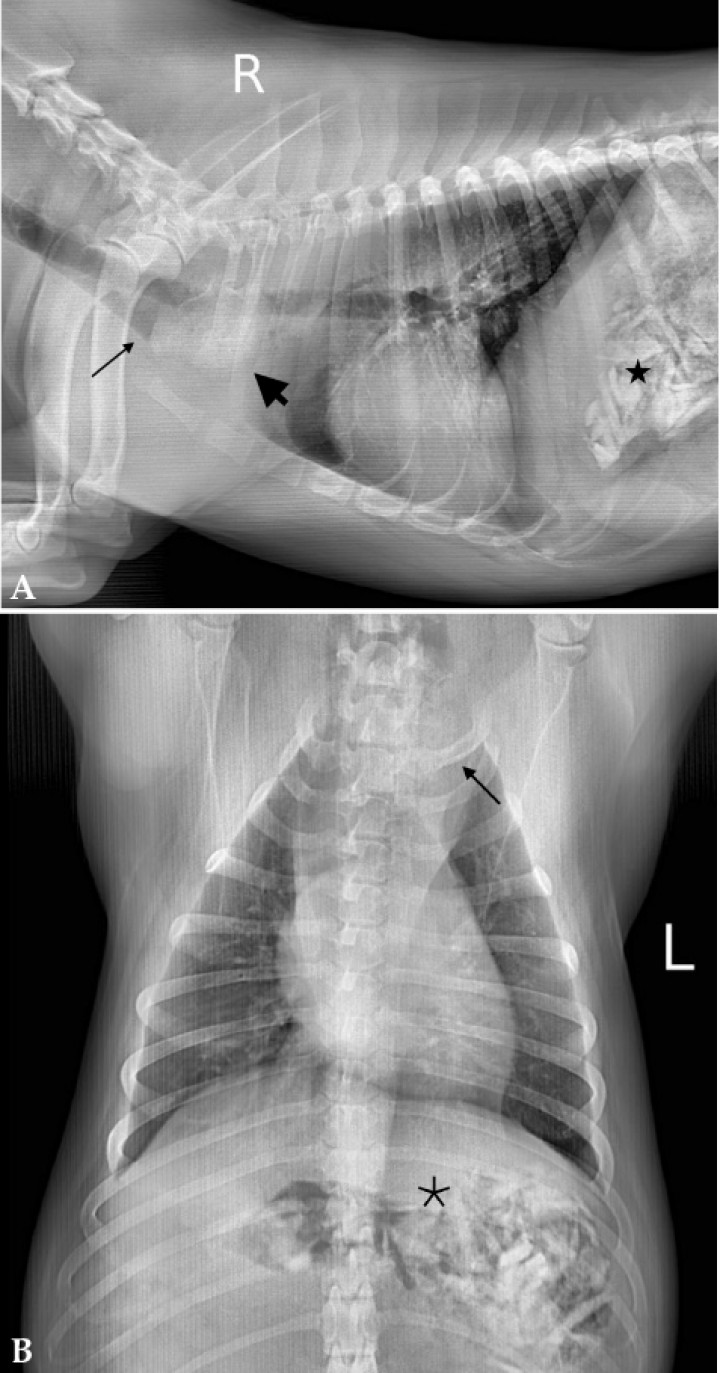

<p>Misma imagen que la Figura 1. (<strong>A</strong>) Radiografía de la cavidad torácica. A nivel de la entrada torácica, se observa una zona con aumento de la opacidad, con densidad hueso (flecha gruesa), el esófago craneal a esta zona está dilatado con acúmulo de gas (flecha fina). En abdomen craneal, se observan en estómago estructuras de distinta forma y tamaño con radiopacidad hueso (asterisco). (<strong>B</strong>) Aumento de la densidad radiográfica en la entrada torácica con aumento de las dimensiones del mediastino craneal (flecha). El estómago contiene numerosas estructuras con densidad hueso (asterisco).</p>

Figura 2

Misma imagen que la Figura 1. (A) Radiografía de la cavidad torácica. A nivel de la entrada torácica, se observa una zona con aumento de la opacidad, con densidad hueso (flecha gruesa), el esófago craneal a esta zona está dilatado con acúmulo de gas (flecha fina). En abdomen craneal, se observan en estómago estructuras de distinta forma y tamaño con radiopacidad hueso (asterisco). (B) Aumento de la densidad radiográfica en la entrada torácica con aumento de las dimensiones del mediastino craneal (flecha). El estómago contiene numerosas estructuras con densidad hueso (asterisco).